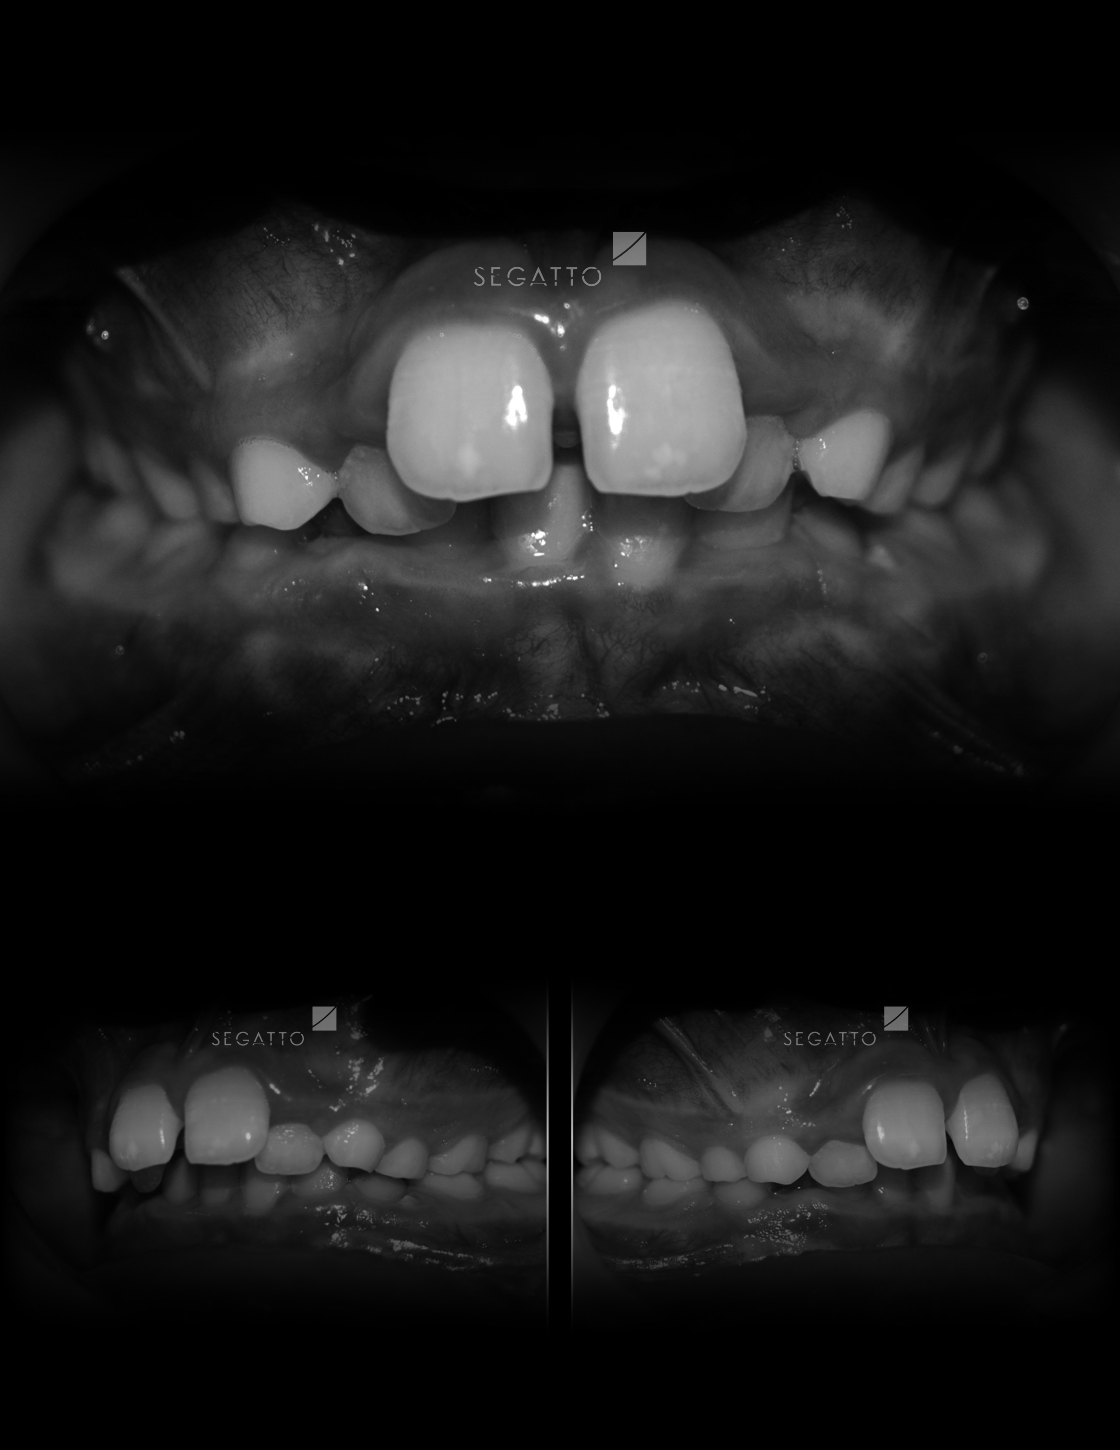

Orthodontics

Cases